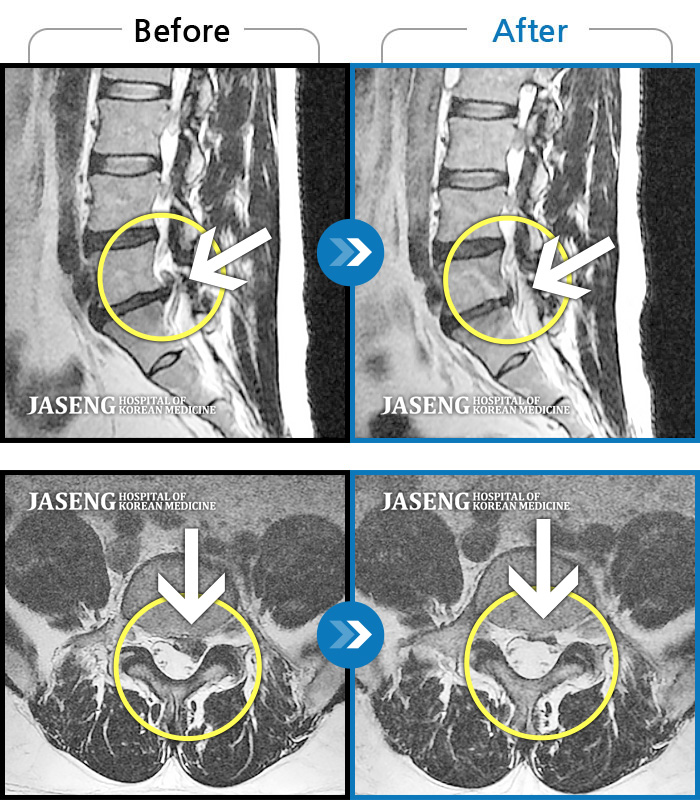

허리디스크

도움받은 사례

일산 · 김진수 원장

처음 내원 시 좌측 엉덩이가 많이 아프고, 좌측 다리로 저림이 심하며 특히 좌위시 하지 방사통이 심하여 1분도 좌위가 어려워 식사도 서서 하는 등 정상적인 활동이 힘든 상태였습니다.

촬영시기

2021.11.12 ~ 2024.07.23

2024.11.08

조회수 588